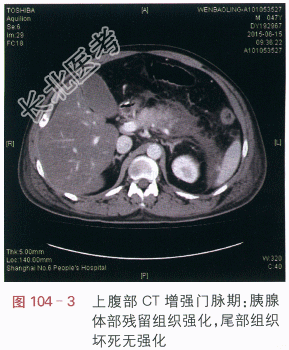

读片分析:CT平扫:胰腺体尾部肿胀,密度减低,边缘模糊,周边见流出影,左肾前筋膜肥厚(见图104-1)。附见:肝脏密度减低。CT增强扫描:胰腺体尾部呈低密度,边缘模糊,胰腺体部残留组织强化,尾部组织坏死无强化(见图104-2~图104-4)。